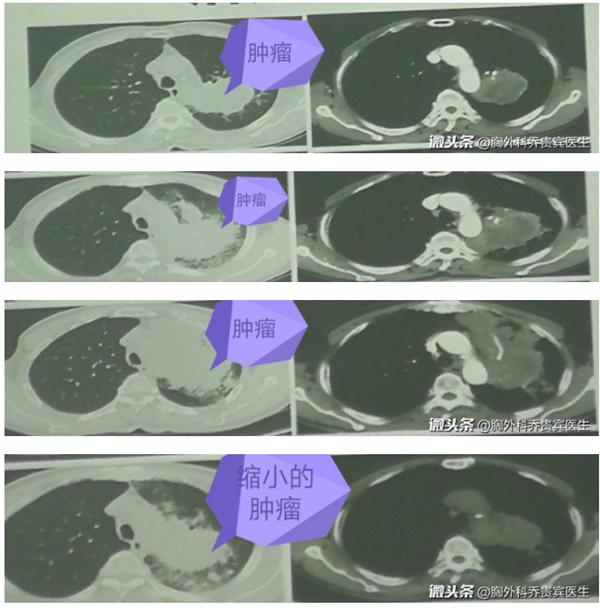

骨转移的肿瘤病人,2次免疫治疗后,肿瘤没变化

因此,我们对这个病人开展了两个疗程的化疗免疫治疗,发现肿瘤没大没小,控制良好。

继续进行第三个疗程的免疫治疗以后,再次评估,发现肿瘤明显增大。

按照传统的评估方法,这个肿瘤似乎已经进展了,需要更改治疗策略。但病人却感觉疼痛和胸闷等症状明显好转,这与影像结果不符。我们考虑为假性进展,造成的原因是,因为大量免疫细胞聚集在肿瘤周围造成了肿块增大的影像。

第4次免疫治疗后,肿瘤缩小了

第四个疗程的免疫治疗后,肿瘤明显缩小。说明免疫细胞攻击肿瘤,杀死了大部分肿瘤,效果显著。

这个病人就是一例临床观察到的假性进展。病人经过两个疗程的治疗以后,病灶没大没小,我们评估稳定。但是第三个周期的治疗后,就出现了肿瘤增大。继续治疗后,肿瘤又明显的缩小了。